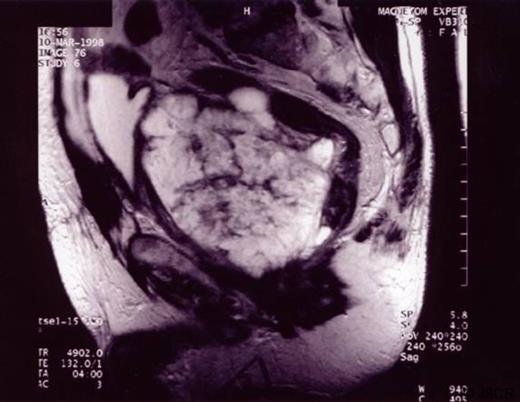

Histology showed mucinous cystadenocarcinoma of the prostate with extracellular mucin involving more than 50% of the specimen which was also PSA positive. Repeat PSA was 56ng/ml and hormonal therapy was initiated. MRI scan showed an enormous multicystic tumour arising from the prostate gland infiltrating the posterior wall of the bladder and also involving the rectum (Figure 1).

MRI scan showing an enormous multicystic tumour arising from the prostate gland infiltrating the posterior wall of the bladder and also involving the rectum